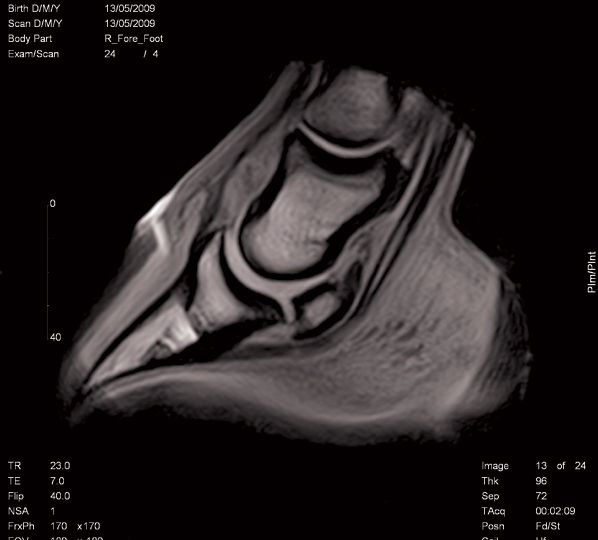

Why you should consider this anatomic anomaly in female dogs with recurrent urinary tract infections-and how you can fix it.